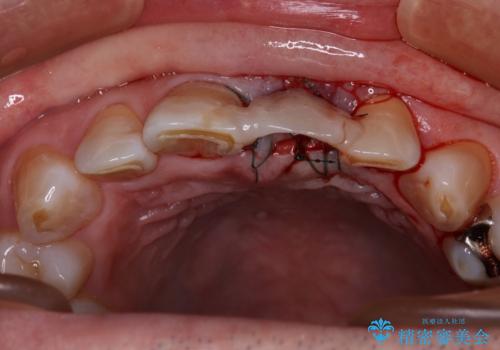

歯茎に溝が 大きく欠損した前歯のインプラント補綴治療

- 歯が朽ちてしまい、歯茎に大きな溝ができていることを気にして来院された患者様です。

インプラント治療を希望されておりましたが、軟組織の欠損が非常に大きいため、骨の回復を待ちながら歯肉の形態を整えていくこととしました。

歯肉形態を概ね回復するタイミングでインプラントを埋入し、補綴治療を行うこととしました。

歯肉移植術による更なる歯肉ラインの改善も検討しましたが、笑ったときに歯肉ラインは唇に隠れてしまうため、現在の位置にて仕上げることとしました。

骨の前後幅が小さかったため、細いインプラントを選択せざるを得ない状況でした。咬合力が非常に強い方のため、就寝時のマウスピース装着を徹底していただき、インプラントへの負担を軽減することとしています。